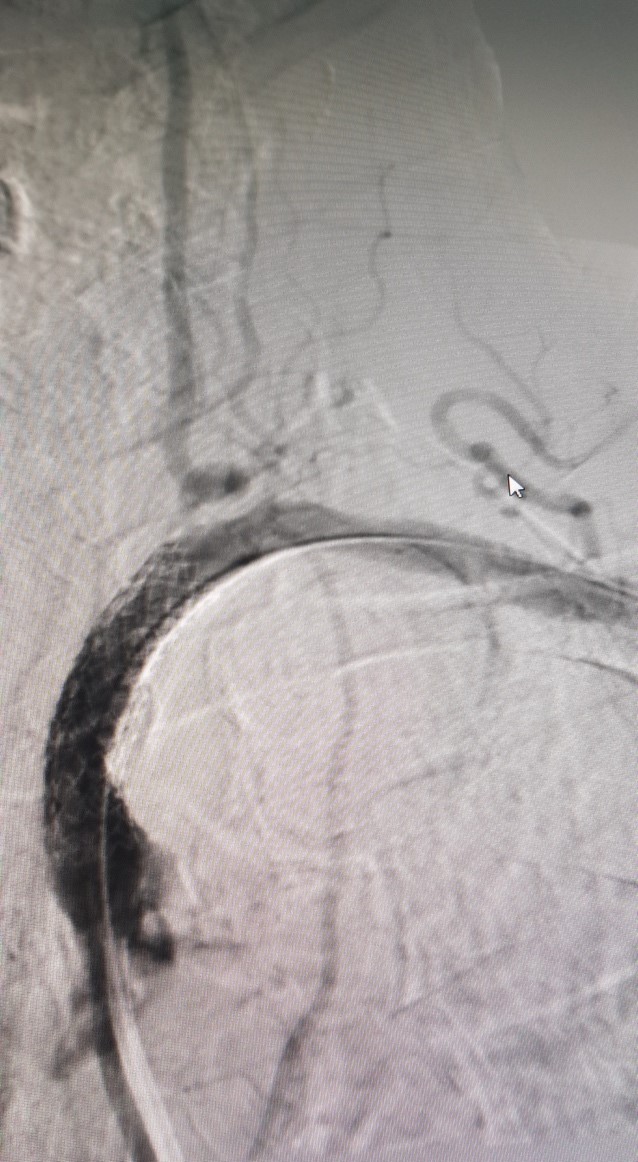

Sau can thiệp

Hình ảnh can thiệp động mạch dưới đòn tại Bệnh viện Đa khoa Tỉnh Quảng Trị